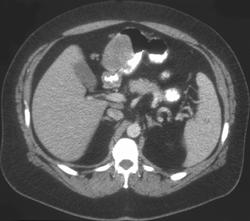

Diagnosis

Gastric Adenocarcinoma